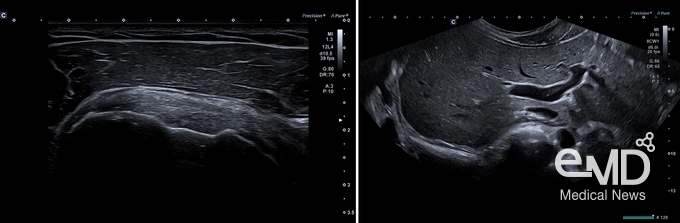

특히 이번에 처음 도입된 '프리시젼 플러스 파인 프로세싱 (Precision+

Fine Processing)' 모드는 신호를 더욱 선명하게 표현하여 이미지의 윤곽선을 뚜렷하게 만든다. 이 기능은 어플리오 비욘드에 처음 적용됐다.

‘프리시젼 플러스 파인 프로세싱’ 적용(왼쪽)과 ‘울트라 와이드

뷰’ 적용(오른쪽)

채택하여 영상의 해상도, 투과력, 균일도를 대폭 향상시켰다. iBeam+ 모드는 새롭게 개발된 초고감도 싱글 크리스탈 트랜스듀서와 결합되어 최적의 성능을 발휘한다. 뿐만 아니라 검사 시 스캔 각도를 최대 140°까지 확장 가능한

울트라 와이드 뷰 (Ultra Wide View)로 볼 수 있어 크기가 큰 간과 같은 장기도 고화질로

한 번에 촬영 가능하다.